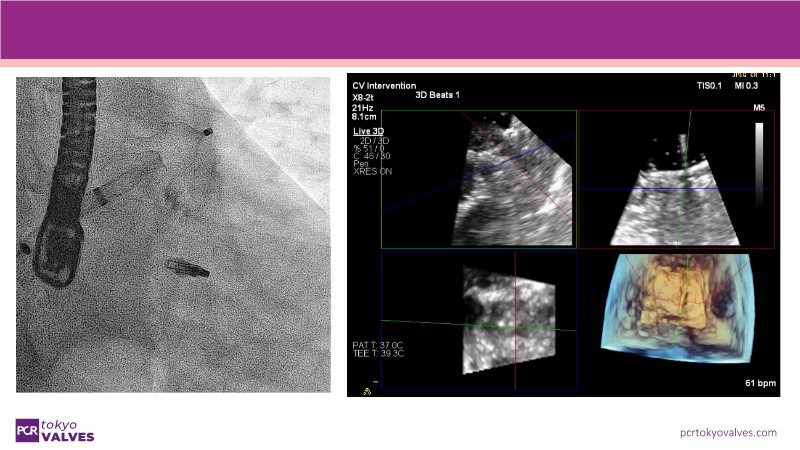

Explore the latest advancements in TEER therapy with this PCR Tokyo Valves 2025 session dedicated to MitraClip. Through expert-led case discussions, gain a deeper understanding of complex scenarios, including restricted posterior leaflet in functional mitral regurgitation, commissure lesion (A3P3), and MitraClip combined with Amulet.

This session also highlights key findings from the OCEAN study, shedding light on 1-year heart failure rehospitalisation outcomes with MitraClip. Additionally, discover how atrioventricular valve morphology impacts treatment strategies and how the four available clip sizes can be used to personalise and optimise TEER outcomes.